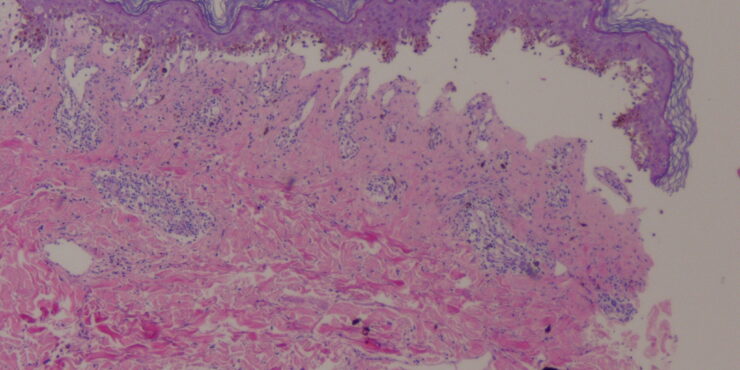

Branchial cleft cyst =كيسة الشق الغلصمي Branchial Cyst (Branchial Cleft Cyst) Sequestration of first or second branchial cleft membranes results in these cysts, sinuses, or tags. EPIDEMIOLOGY Branchial cleft cysts are largely sporadic, but autosomal dominant cases have been reported. There is no gender predominance. Ten percent of lesions are bilateral. ETIOLOGY AND […]